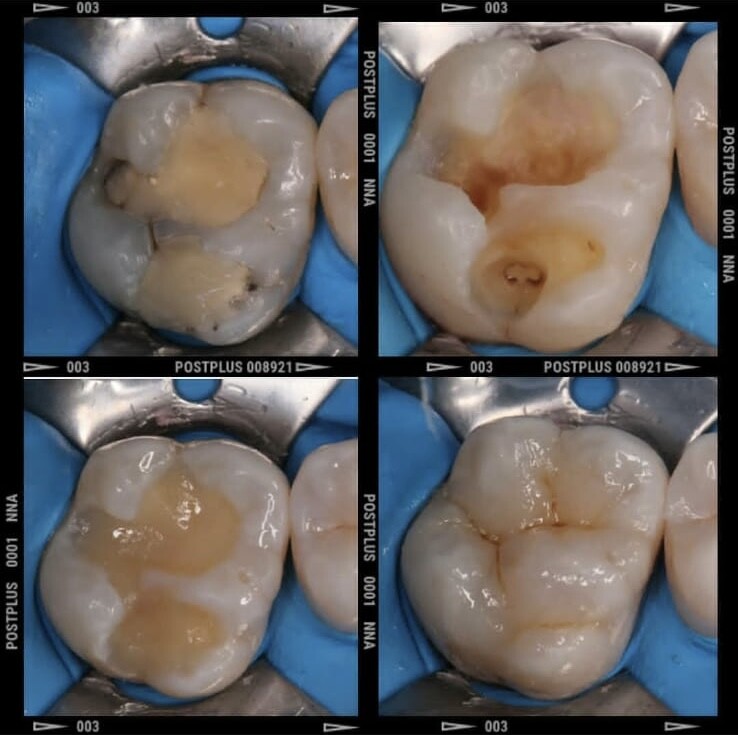

Лечение зубов

Лечение кариеса

Пломбирование зубов

Лечение пульпита

Пломбы быстро выпадали или были неэстетичными, под пломбами возникал кариес, под коронками портились зубы, после лечения корневых каналов возникали кисты, после снятия брекетов зубы опять разъезжались.